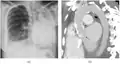

Extensive left-sided fibrothorax

Chest radiograph displaying inhomogeneous opacification of the left half of the chest that is fibrothorax